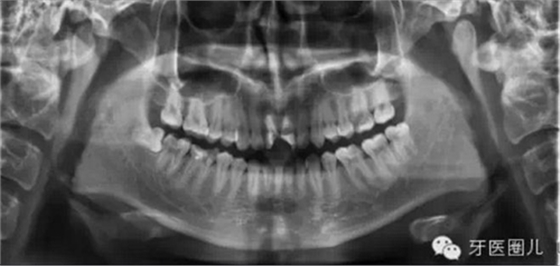

1.確定工作長(zhǎng)度(根測(cè)儀+X光片)這個(gè)大家都知道就不再贅述

觀察術(shù)前X光片,設(shè)想達(dá)到一個(gè)理想的結(jié)果,然后用這一設(shè)想來(lái)指導(dǎo)每一治療步驟,這樣自然會(huì)提高我們的根管治療的操作水平。